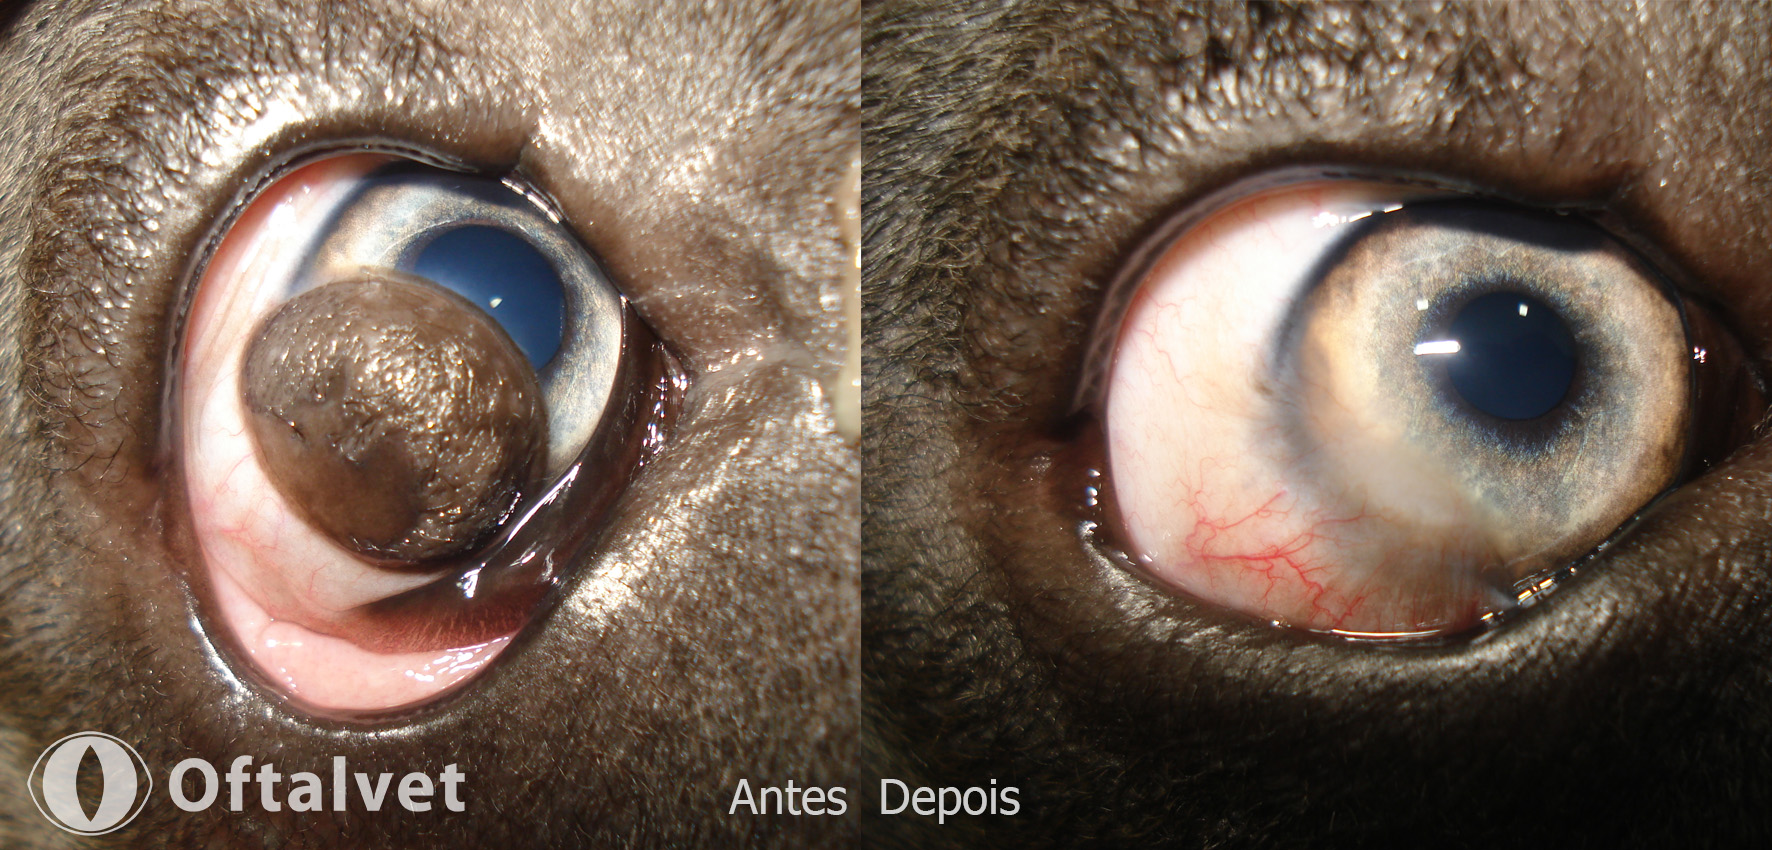

Nas patologias oftálmicas, o intervalo de tempo decorrido entre o inicio dos sintomas e a implementação do tratamento médico ou cirurgico, é fundamental para um desfecho de sucesso.